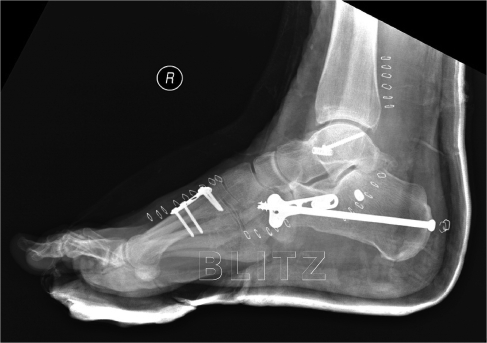

High-Resolution US and MR Imaging of Peroneal Tendon Injuries